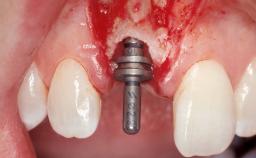

Late Flapless Placement of an Implant in a Maxillary Left Central Incisor Site

Placement Protocol Early or late implant placement

Bone Volume Deficient horizontally, requiring prior grafting

Bone Augmentation Horizontal|Staged

Soft Tissue Grafting Simultaneous